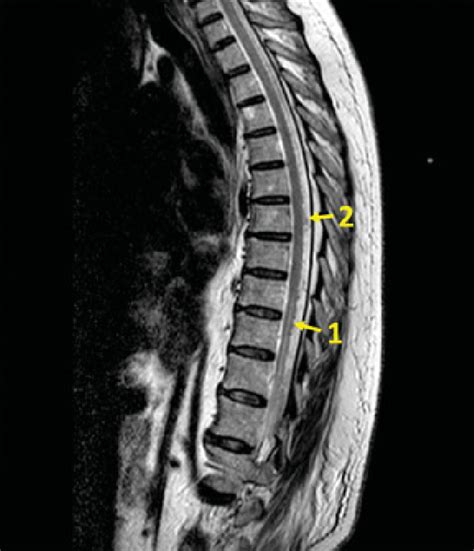

So, if you suspect there’s an issue with the medullary cone region , how do doctors figure it out, and what can be done? Diagnosis typically starts with a thorough medical history and a detailed neurological examination. Your doctor will be looking for specific patterns of weakness, sensory loss, and reflex changes in your legs and trunk, as well as assessing bowel and bladder function. To get a clear picture of what’s going on inside, imaging studies are crucial. Magnetic Resonance Imaging (MRI) is usually the gold standard. It provides detailed images of the spinal cord, nerve roots, and surrounding structures, allowing doctors to identify things like tethered cords, disc herniations, tumors, or other abnormalities affecting the conus medullaris. Sometimes, a CT scan might be used, especially if MRI is contraindicated or to get a different perspective on bony structures. In some cases, electromyography (EMG) and nerve conduction studies might be performed to assess the electrical activity of the nerves and muscles, helping to pinpoint the extent of nerve damage.

Alright, let’s get a bit more specific about the medullary cone region . Anatomically, the spinal cord extends from the brainstem all the way down. In adults, it typically ends around the level of the first or second lumbar vertebra (L1/L2). Below this point, the spinal cord transitions into a collection of nerves that look like a horse’s tail – this is called the cauda equina. The medullary cone is the actual cone-shaped termination of the spinal cord itself, sitting just superior to the cauda equina. It’s a marvel of biological engineering, really. This tapered end houses the lower sacral and coccygeal nerve roots, which are super important for those critical functions we mentioned. Understanding this transition is key because problems in this area can have significant and varied impacts. The exact level where the conus medullaris ends can vary slightly from person to person, and even change a bit throughout childhood as the vertebral column grows faster than the spinal cord. So, while L1/L2 is the typical adult landmark, it’s not an absolute hard rule. The surrounding meninges, the protective layers around the spinal cord, also extend further down, forming the sac that contains the cauda equina. This whole setup is designed for protection and function, ensuring that the delicate nerve tissue is shielded while still allowing for the necessary signals to travel to and from the brain.